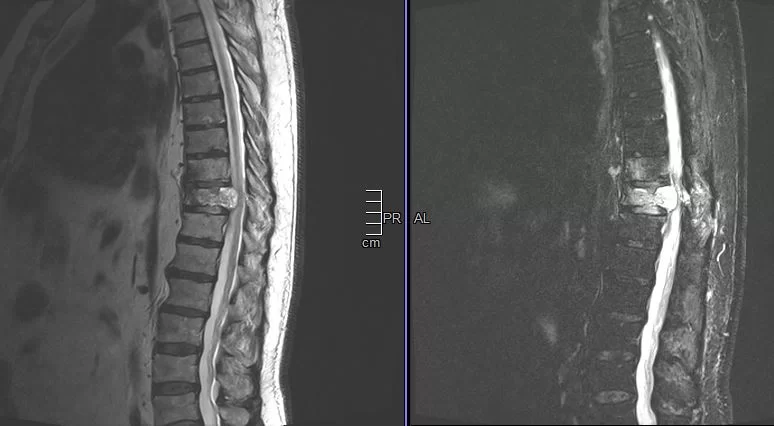

Ο απεικονιστικός έλεγχος με μαγνητική και αξονική τομογραφία της σπονδυλικής στήλης ανέδειξε μάζα κυρίως στο σώμα του 10ου θωρακικού σπονδύλου (Θ10) με περιβρογχισμό και πίεση επί του νωτιαίου μυελού. (Σημειώστε και τη διήθηση του Θ9 σπονδύλου, χωρίς οστεόλυση).